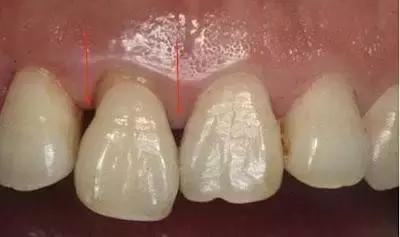

如果两颗牙齿之间的牙龈乳头畏缩(牙龈萎缩),就会造成两颗牙齿之间下方出现空隙,食物就比较容易在嘴唇、脸颊和舌头的运动作用下,水平地进入了间隙,造成了“卡肉”的现象。

牙龈萎缩,需要考虑系统的牙周治疗或手术。